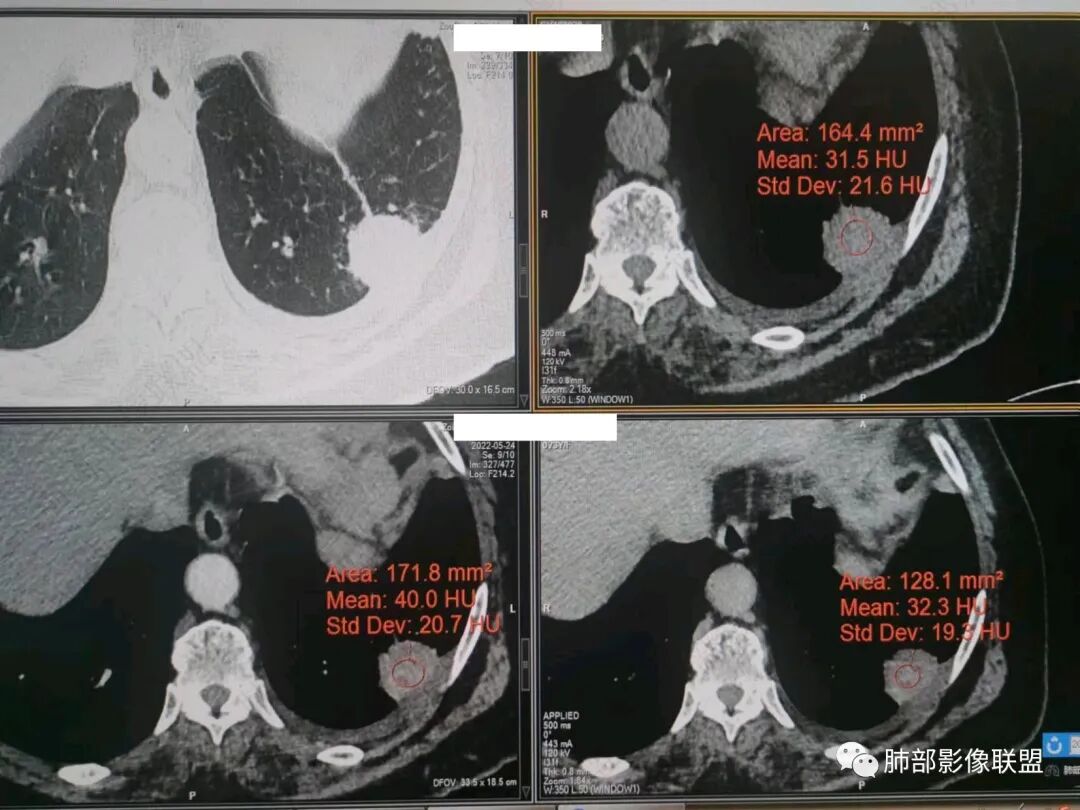

秦化君:左肺下叶外基底段胸膜下软组织密度结节性,边缘毛糙与血管相连,密度不均,增强后病灶内边界不清低密度区,胸膜栽桩,少量胸腔积液。考虑恶性病变,腺癌可能。真菌待排。

谢加平:老年女性,慢性咳嗽,咳白痰史,左肺下叶后基底段胸膜下肿块,类圆形,边界清膨隆,密度不均匀,低强化及小灶性坏死,坏死轮廊不清,胸膜下栽赃明显,左侧胸腔少量积液,向胸壁肌侵犯,另肿块近心侧见支指套征,粘液低密度,支持恶性,粘液腺Ca,经皮肺穿刺活检明确诊断。

361度:老年女性,发热,胸部CT示左下肺胸膜下结节影,血管集束,毛棘,密度不均,胸膜栽赃,少量胸腔积液,不均匀强化,坏死边界不清,肿标轻微升高,考虑恶性,鳞癌合并感染。

红星:老年女性患者。胸膜下结节病变,明显的膨胀,并局部侵犯胸膜,增强明显的强化。病灶周围带有局灶的渗出性改变以及条索上的影。考虑腺癌的可能性大,鉴别结核肉芽肿性病变。

袁媛:左肺下叶胸膜下球形肿块,宽基底连于胸膜下,胸膜栽赃,边缘膨隆,有血管供应,增强有强化,考虑腺癌。

看图说话:胸膜下肿块,密度不均,边缘毛糙,增强后不均匀强化,胸膜栽赃,左侧胸腔积液,腺癌,鉴别肉芽肿。

人生海海:左肺下叶不规则形软组织密度影,膨隆生长,边缘清楚,分叶,棘突征,支气管截断,血管纠集,病灶轻度强化、内多发坏死,左侧少量胸腔积液,考虑粘液腺癌,鉴别肺脓肿。

位移:老年女性,左肺下叶肺胸膜下团块影,边界清、毛糙,膨隆,内密度不均,不均匀强化,内见坏死,胸膜栽赃,胸腔少量积液,首先考虑恶性肿瘤,低分化腺癌,鉴别小细胞癌,炎性假瘤。

放射线:左肺下叶后基底段胸膜下肿块,边缘膨隆,密度不均匀,内见低密度坏死,胸膜栽赃,左侧胸腔少量积液,考虑恶性,腺癌?鉴别放线菌,OP伴脓肿。